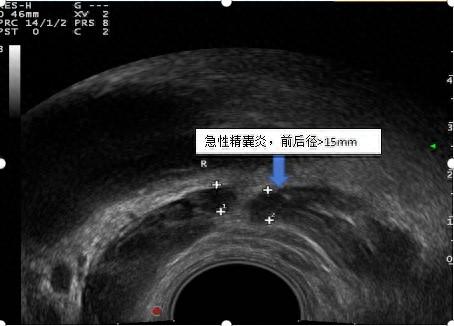

血精是因为前列腺炎吗?"真凶"原来是它